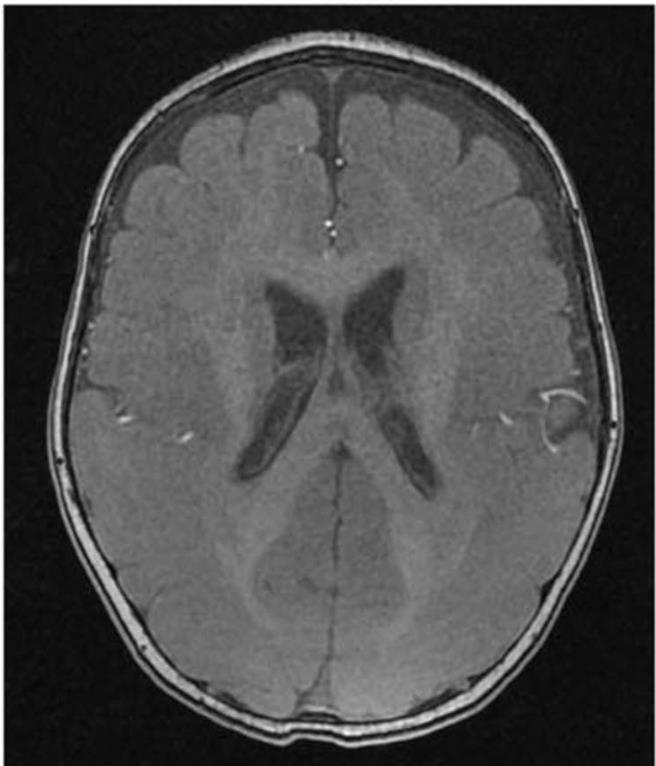

蔡孟翰說,高雄長庚長期研究台灣的平腦症,發現一位頑固型癲癇病患合併有平腦症的病人,安排腦部核磁共振後發現,病人後方的大腦區域腦迴發育有異常,產生大腦表面平滑的現象,進一步用最新次世代定序技術研究發現,是由一個從未被發表過的新基因NDEL1突變,所導致的平腦症合併癲癇症。